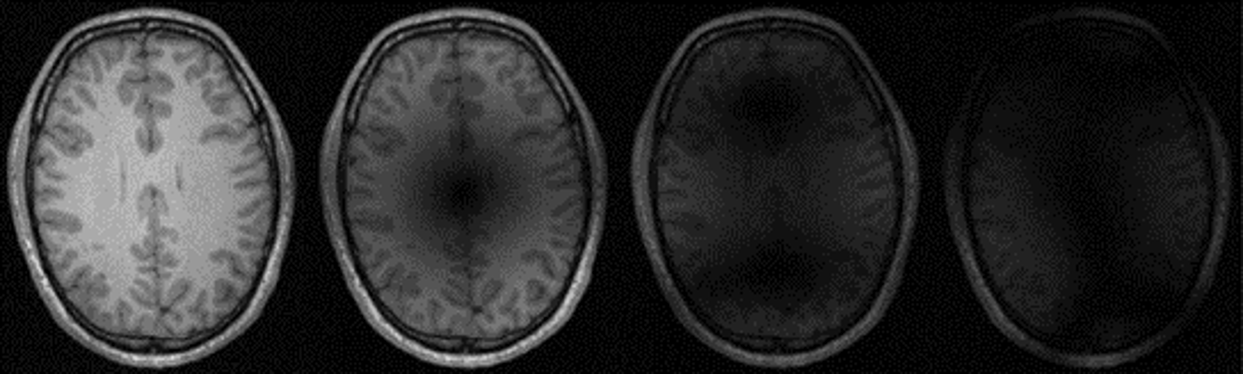

Example reconstructions of brain data are shown in Fig. 5(a) and Fig. 5(b), from the CC359 dataset, and Fig. 6(a) and Fig. 6(b), from the fastMRIBrain dataset. Figure 7 shows example reconstructions of knee data from the StanfordKnee dataset.

(a) fastMRIBrains 14-coil data - 4x acceleration

Refer to caption

(b) fastMRIBrains 14-coil data - 8x acceleration

Figure 6: Reconstructions of 14-coil T2-weighted data from the fastMRI Brains dataset, undersampled with an Equispaced 1D sampling pattern for 4x (Fig. 6(a)) and 8x (Fig. 6(b)) acceleration. The top row-first column shows the ground truth (Target) image. SSIM and PSNR scores are reported for each method and computed against the Target image. Methods are sorted alphabetically.